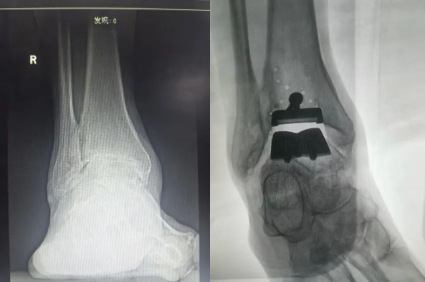

近日,济宁市第一人民医院手外科足踝外科主任曾文超教授团队成功应用3D打印技术,为一名77岁的严重右侧踝关节骨性关节炎患者成功实施了3D打印全踝关节置换手术,比传统踝关节置换时间减少90分钟,比术前踝关节活动度增加30度,标志着手外足踝外团队在关节重建领域迈入“个体化精准修复”新阶段。

术中应用术前设计好3D模具设计截骨走形,置入截骨导板,精准截骨纠正患者距骨外翻力线,手术过程顺利。术后假体位置及力线良好,肢体畸形明显纠正。

随着人工智能兴起,数字骨科逐渐成熟,术前根据踝关节CT数据,3D建模,模拟截骨推演术中截骨矫正力线,从而缩短手术截骨调整力线时间,提高截骨精准度。此次手术的完成,填补了鲁西南地区在该领域的医疗技术空白,济宁市第一人民医院手外科足踝外科继成功开展全踝关节置换技术后,在足踝疾病诊疗领域再次取得的重大突破。